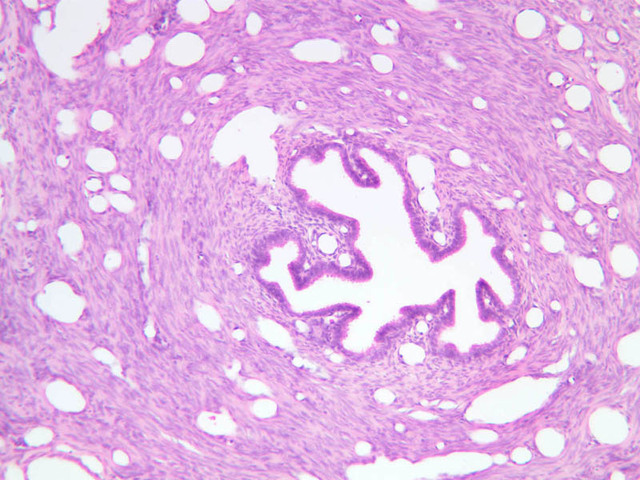

The endometrium of the cervical canal does not slough during the menstrual phase. The glands in this region are relatively large and extensively branched. They are lined by a tall simple columnar epithelium very active in the secretion of mucus. Occasionally these glands become blocked forming Nabothian cysts. The transition of the epithelium of the cervix to that of the vagina is abrupt and is in the region of the external os. At this point, the cervical simple columnar is replaced by the vaginal stratified squamous epithelium (slide B-98 [2.5x-labeled, 10x, 20x, 40x] [2.5x, 10x, 20x, 40x]). This is an area which is commonly inflamed as well as a primary location of cervical cancer.